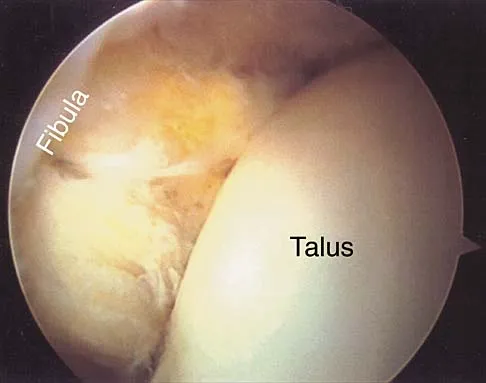

Question 20

Figure 24 shows the arthroscopic view of a patient with ankle impingement syndrome. This is commonly seen after high ankle sprains and represents fibrotic granulation thickening of what structure?

Explanation